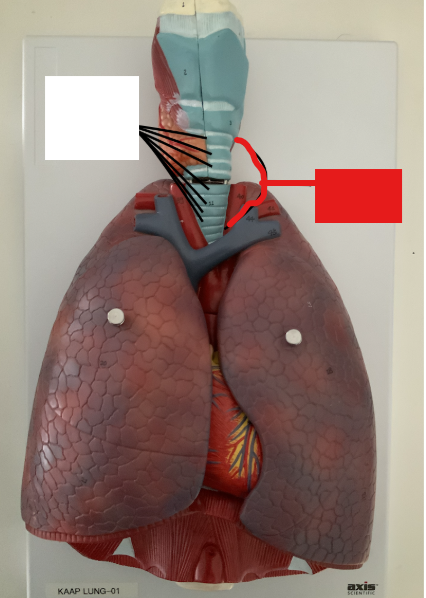

What structure is this?

Right main bronchus

What structure is this?

Right superior lobar bronchus

What structure is this?

Middle Lobar bronchus

What structure is this?

Right inferior lobar bronchus

What structure is this?

Left main bronchus

What structure is this?

Left superior lobar bronchus

What structure is this?

Left inferior lobar bronchus

What structure is this?

The carina

Horizontal fissure of right lung

What structure is this?

Oblique fissure of right lung

What structure is this?

Oblique fissure of left lung